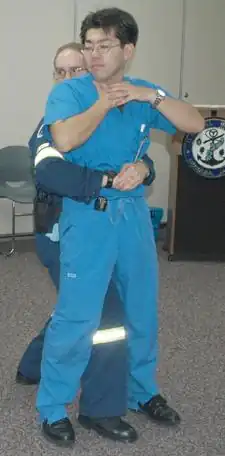

| A demonstration of abdominal thrusts on a person showing signs of choking | |

Abdominal thrusts (Heimlich maneuver)

Abdominal thrusts[37] are performed with the rescuer embracing the belly of the choking victim from behind. Then, the rescuer closes their own dominant hand, grasps it with the other hand, and presses forcefully with them on the area located between the chest and the belly button of the victim, in a direction of in-and-up. This method tries to create enough pressure upwards to expel the object that obstructs the airway. The strength is not focused directly against the ribs, to avoid breaking them. If the first thrust does not solve the choking, it can be repeated several times.

The use of abdominal thrusts is not recommended for infants under 1 year of age due to risk of causing injury, so there are adaptations for babies (see more details further below), but a child that is too big for the babies' adaptations would require normal abdominal thrusts (according to the size of the body). Besides, abdominal thrusts should not be used when the victim's abdomen presents problems to receive them, such as pregnancy or excessive size; in these cases, chest thrusts are advised (see more details further below).

Although it is a well known method for choking intervention, the Heimlich Maneuver is backed by limited evidence and unclear guidelines. The use of the maneuver has saved many lives but can produce deleterious consequences if not performed correctly. This includes rib fracture, perforation of the jejunum, diaphragmatic herniation, among others.[38]